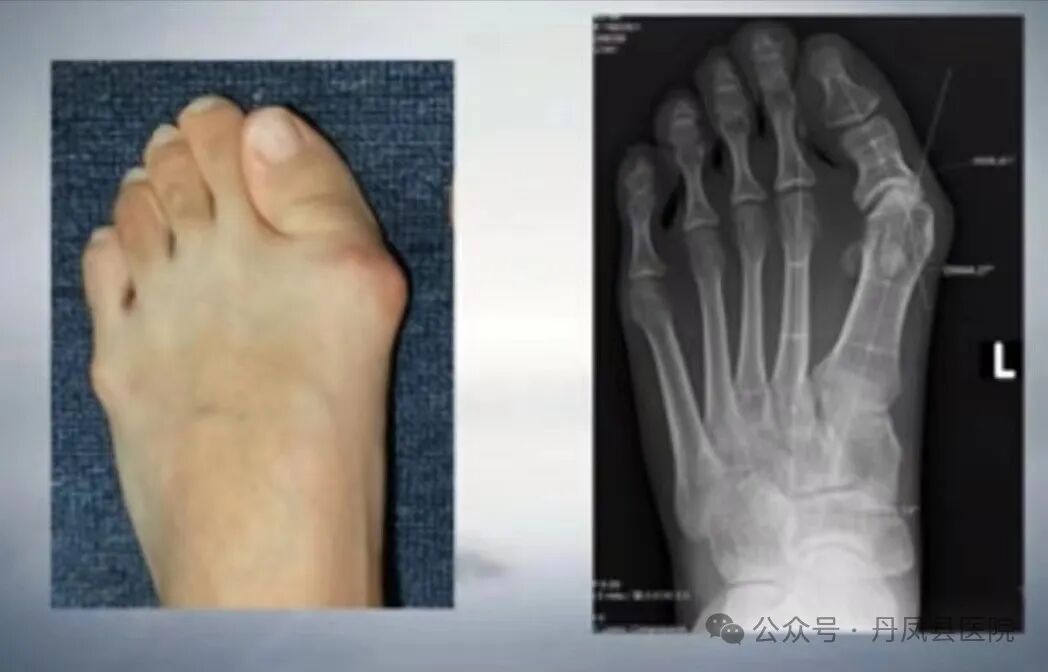

病例二:患者张某,女,42岁,左足拇外翻畸形3年余,行走疼痛,已严重影响到日常生活,经多方打听,来到我院骨一科就诊。收治入院后,骨一科主任李静宏带领科室团队为其进行了全面的足部检查,充分评估病情,研究手术治疗方案,最终成功为患者实施了拇外翻矫形术。术后患者恢复良好,并不停的称赞:“丹凤县医院医生的技术太好了,使我摆脱了多年来“大脚骨”的烦恼。”

![]()

图为患者术前足部图片